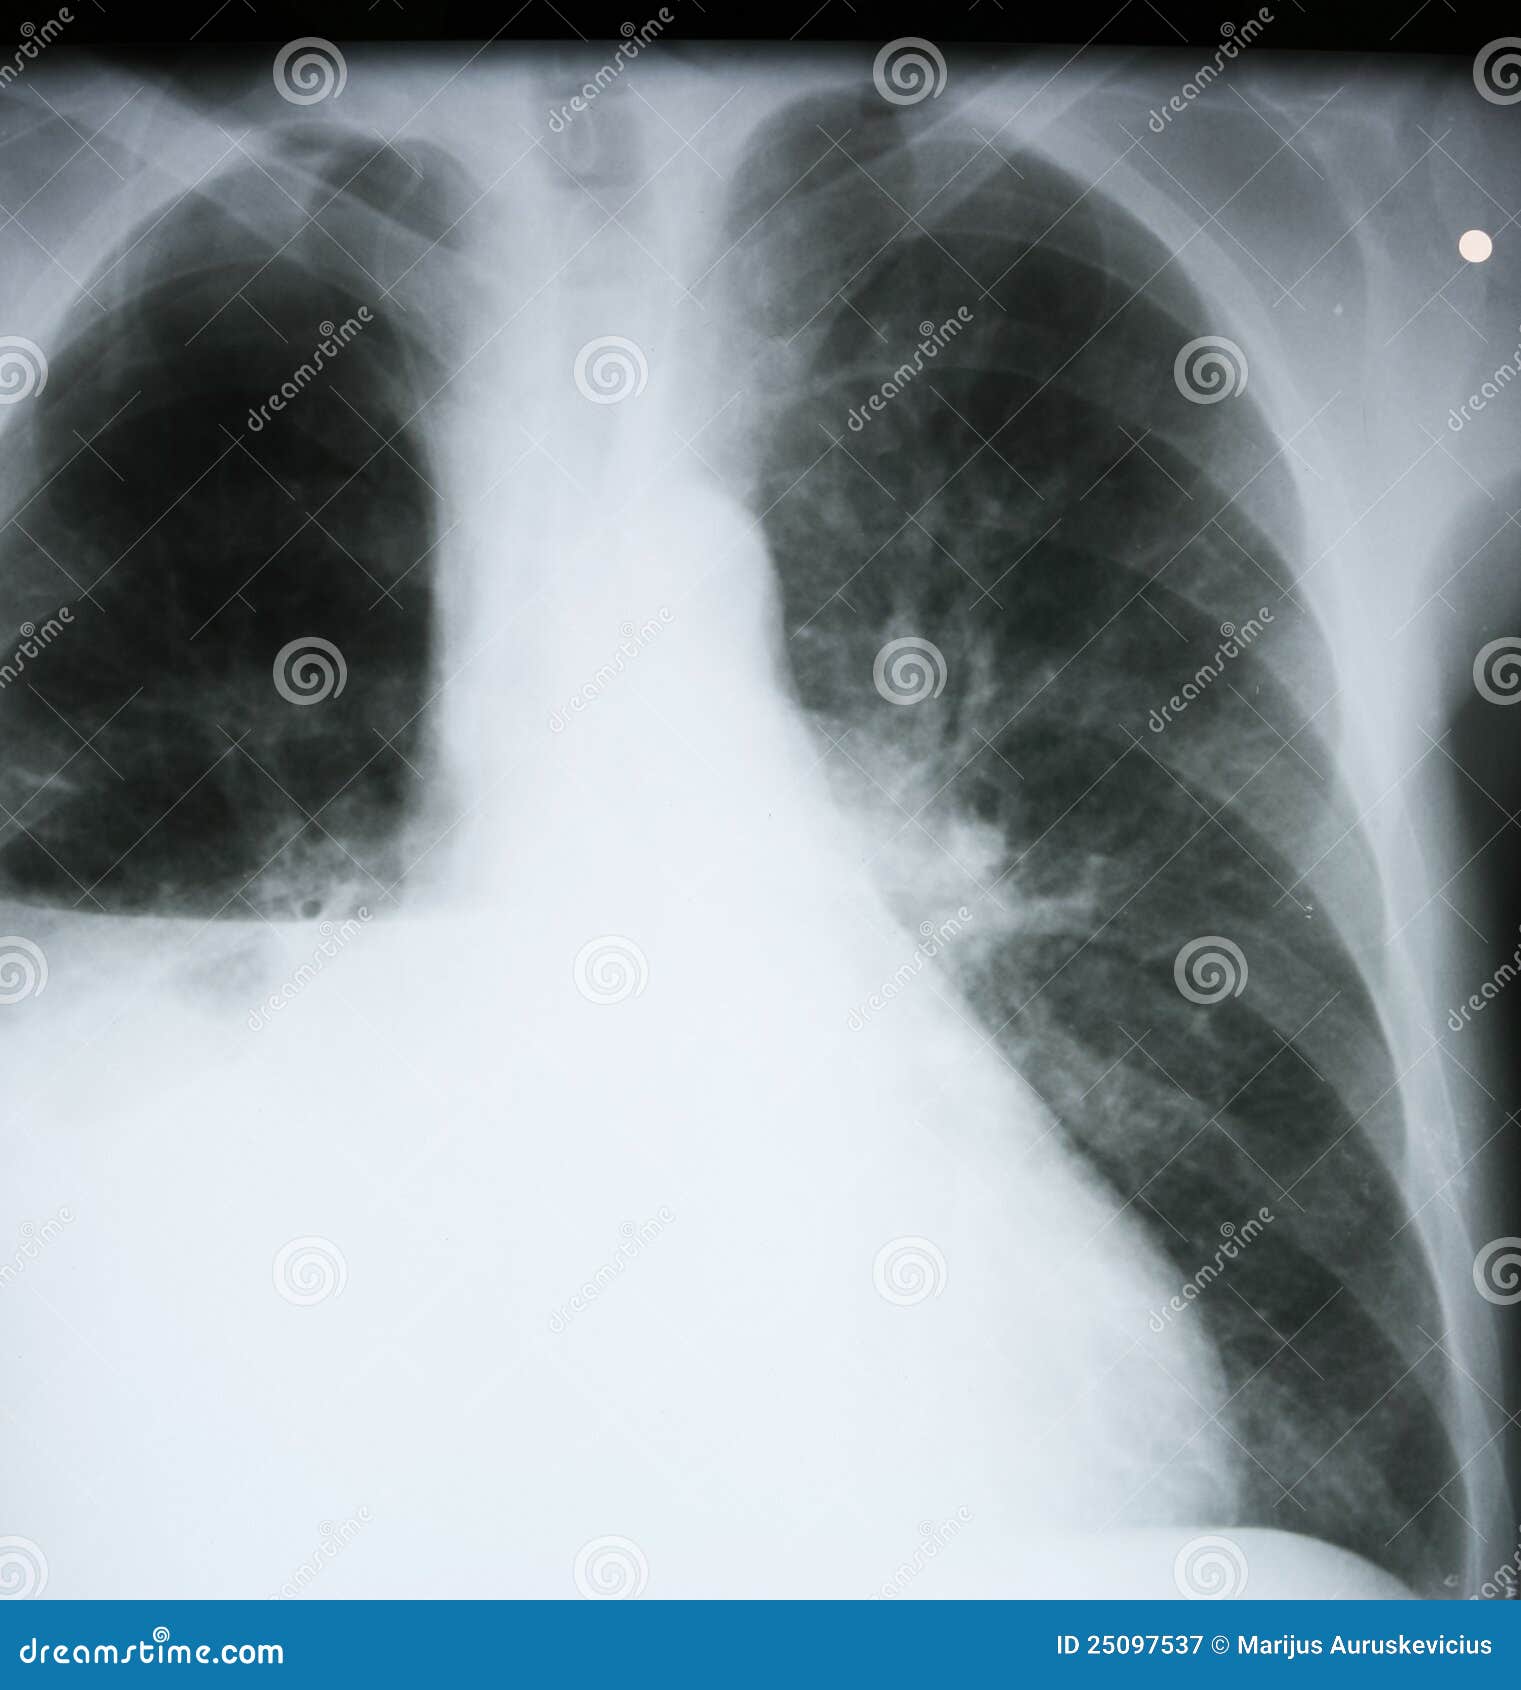

How to read a chest x ray (with pictures) wikihow. Radiology and medical imaging tutorials for uk medical students chest xray airways and lung collapse large pleural effusion chest xray image.

Pleural effusion wikipedia. Diagnosis. Docs can use some extraordinary imaging scans to diagnose the pleural thickening xray the situation is typically first spotted thru a chest xray, in. Mesothelioma chest x ray mesothelioma chest x ray search now. Over 85 million visitors. A way to read a chest x ray (with photos) wikihow. Radiology and medical imaging tutorials for uk medical college students chest xray airlines and lung crumble huge pleural effusion chest xray picture. Mesothelioma chest x ray mesothelioma chest x ray search now. Search for mesothelioma chest x ray. Find quick consequences and discover solutions now! Mesothelioma what is malignant mesothelioma cancer. Mesothelioma is a rare, aggressive cancer caused by asbestos publicity. Approximately three,000 new instances are diagnosed each year in the u.S. Mesothelioma chest x ray browse outcomes right away. Over eighty five million visitors.